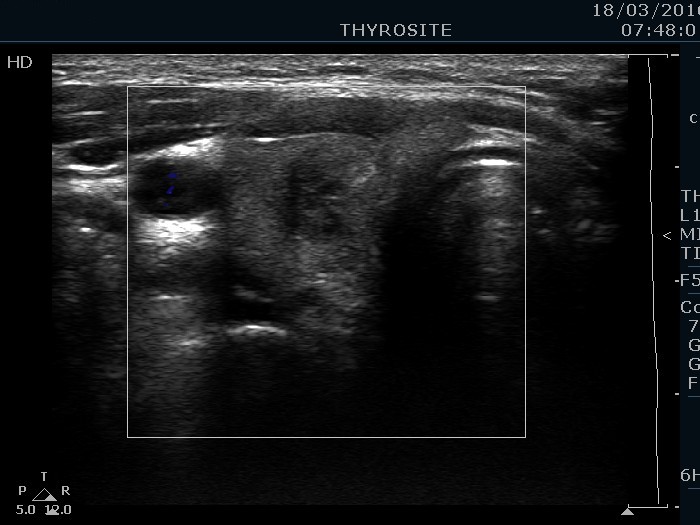

Right lobe, longitudinal scan

Right lobe, transverse scan, color Doppler mode. The lesion is avascular.